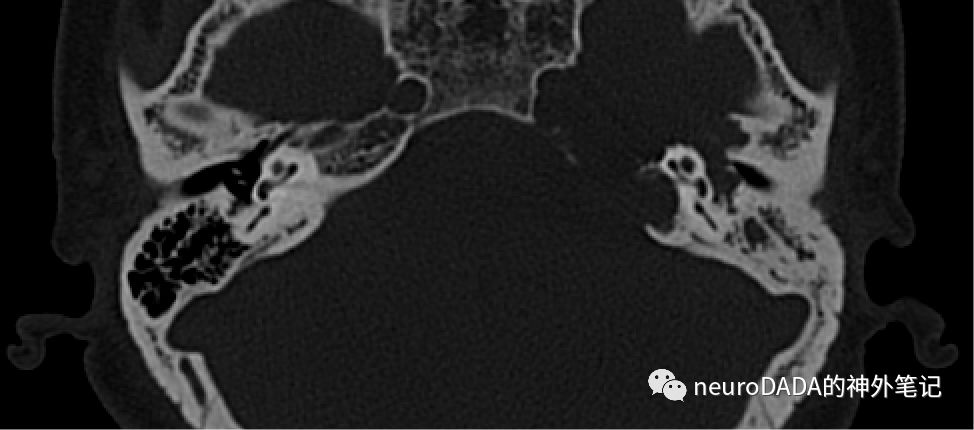

颞骨HRCT

可显示ICA管、骨性迷路、听小骨、内听道、颈静脉孔、咽鼓管、卵圆孔和棘孔等,由此来确定骨性边界。通过3D slicer自行调整切割线。先看轴位,从上到下:

此时可见双侧上半规管,但左侧上半规管前方骨质已受侵蚀,提示术中若经颞下硬膜外入路,看到的骨质缺损的后界即大致为弓状隆起-上半规管的前缘。

此层面可见双侧的半规管都完整,右侧可见内听道上部及发出的面神经迷路段、膝状神经节和鼓室段,左侧则缺如上述结构,且缺损范围包含内听道前方的岩尖和后方的内听道后唇。这基本提示了病变的前后骨性边界。右侧尚可见鼓室及其内的锤骨头、砧骨体的最上部分,以及耳蜗中转的一部分,左侧可在下一层面显示。

此时可观察到双侧的前庭、外侧半规管和后半规管、耳蜗中转、锤骨头和砧骨体,但右侧完好的面神经鼓室段、内听道、岩尖、内听道后唇则在左侧均已侵蚀,两侧的乳突气房也差异明显。

此层面可见双侧耳蜗底转、后半规管、鼓膜、外耳道均完好,右侧可见中耳、乳突气房、咽鼓管内的空气信号正常,而左侧则异常。

此层面用来观察ICA管,可见双侧ICA管的外侧壁、咽鼓管均正常,左侧卵圆孔和棘孔也都正常,基本排除了三叉神经鞘瘤的可能。左侧ICA内侧壁缺失,提示术中有损伤ICA内侧壁的风险。左侧颈静脉球高位,也是术中需警惕的危险因素。另可见此内听道下方层面的左侧岩骨后壁仍有一层不完整的骨皮质与后颅窝硬脑膜相隔。不知术中是保护还是障碍。

该层面为ICA岩骨段的入口水平,可见左侧病灶向下一直扩大岩斜裂,侵蚀了岩尖下部、枕骨的颈静脉结节,分隔颈静脉孔岩部和乙状部的颞骨颈内突、以及分隔颈静脉孔和ICA管外口的颈动脉嵴骨质,均只剩菲薄一层。枕骨的颈静脉突即颈静脉孔的后界尚未受侵。乳突气房继续异常。这也是病变的骨性下界。

再来看冠状位,从前往后:

此处在病灶前界的前方,可见双侧翼管和卵圆孔均正常。

破裂孔层面,左侧的岩尖、斜坡均已出现破坏。

ICA管水平段层面,继续显示左侧岩尖破坏,斜坡骨质也向内侧受推挤。左侧ICA管的外侧壁和咽鼓管尚正常。

耳蜗层面,可见左侧耳蜗、锤骨和鼓膜均尚存,但岩尖明显破坏,耳蜗上表面裸露,鼓室顶壁骨质缺如,鼓室腔受侵,提示术中将显露上述结构。

内听道层面,左侧内听道顶壁缺如,内听道口可有零星骨质残存。

内听道后部、半规管层面,可见左侧半规管完整,上半规管顶壁骨质、即弓状隆起尚存。

颈静脉球层面,可见左侧颈静脉球高位,顶壁缺如,与病变腔沟通,术中有颈静脉球受损风险。面神经乳突段可见完好。

后半规管层面,颈静脉球后部上方仍有部分病变,其顶壁骨质残存,提示术中需要磨除此部分骨质。

前庭导水管层面,双侧均完好,肿瘤后界在此之前。